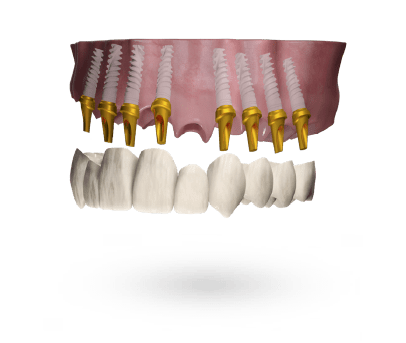

Wybierz rodzaj uzupełnienia

Wybierz platformę